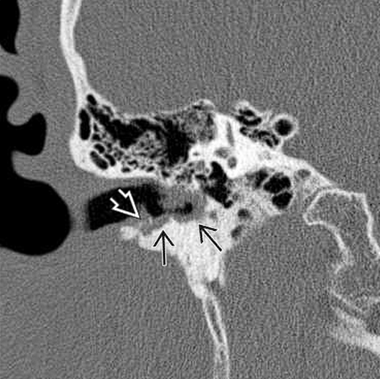

El colesteatoma del conducto auditivo externo se observa en la Tomografía computarizada simple de oído como una lesión con densidad a tejidos blandos en el CAE con erosión ósea asociada y fragmentos óseos intralesionales (Figura 6). La erosión ósea adyacente a la lesión de tejido blando puede ser lisa, similar a un colesteatoma del oído medio; sin embargo, la erosión puede ser irregular debido al hueso necrótico y la periostitis. Por lo general, las paredes inferior y/o posterior están involucradas. Es importante evaluar la extensión hacia la cavidad del oído medio y la integridad del canal del nervio facial, tegmen timpánico y celdillas mastoideas, ya que estas características pueden cambiar el manejo quirúrgico. Es importante destacar que, aunque la resonancia magnética es ampliamente utilizada en la evaluación de enfermedades del oído interno y medio, su utilidad en el diagnóstico de colesteatoma del conducto auditivo externo es limitada. La secuencia de difusión puede llegar a ser de utilidad para la realización de diagnósticos diferenciales con otras lesiones del CAE.

(Figura 6). Corte coronal. Muestra un CCAE como una lesión submucosa erosiva y dentada en el CAE óseo inferior.

Se observa erosión ósea con fragmentos óseos dentro de la matriz del colesteatoma.